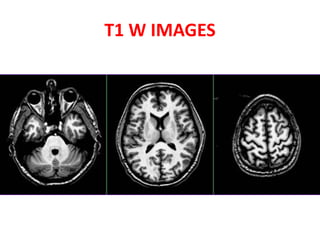

• SHORT TE

• SHORT TR

• BETTER ANATOMICAL DETAILS

• FLUID DARK

• GRAY MATTER GRAY

• WHITE MATTER WHITE

T1 W IMAGES

• SHORT TE •SHORT TR • BETTER ANATOMICAL DETAILS • FLUID DARK • GRAY MATTER GRAY • WHITE MATTER WHITE T1 W IMAGES